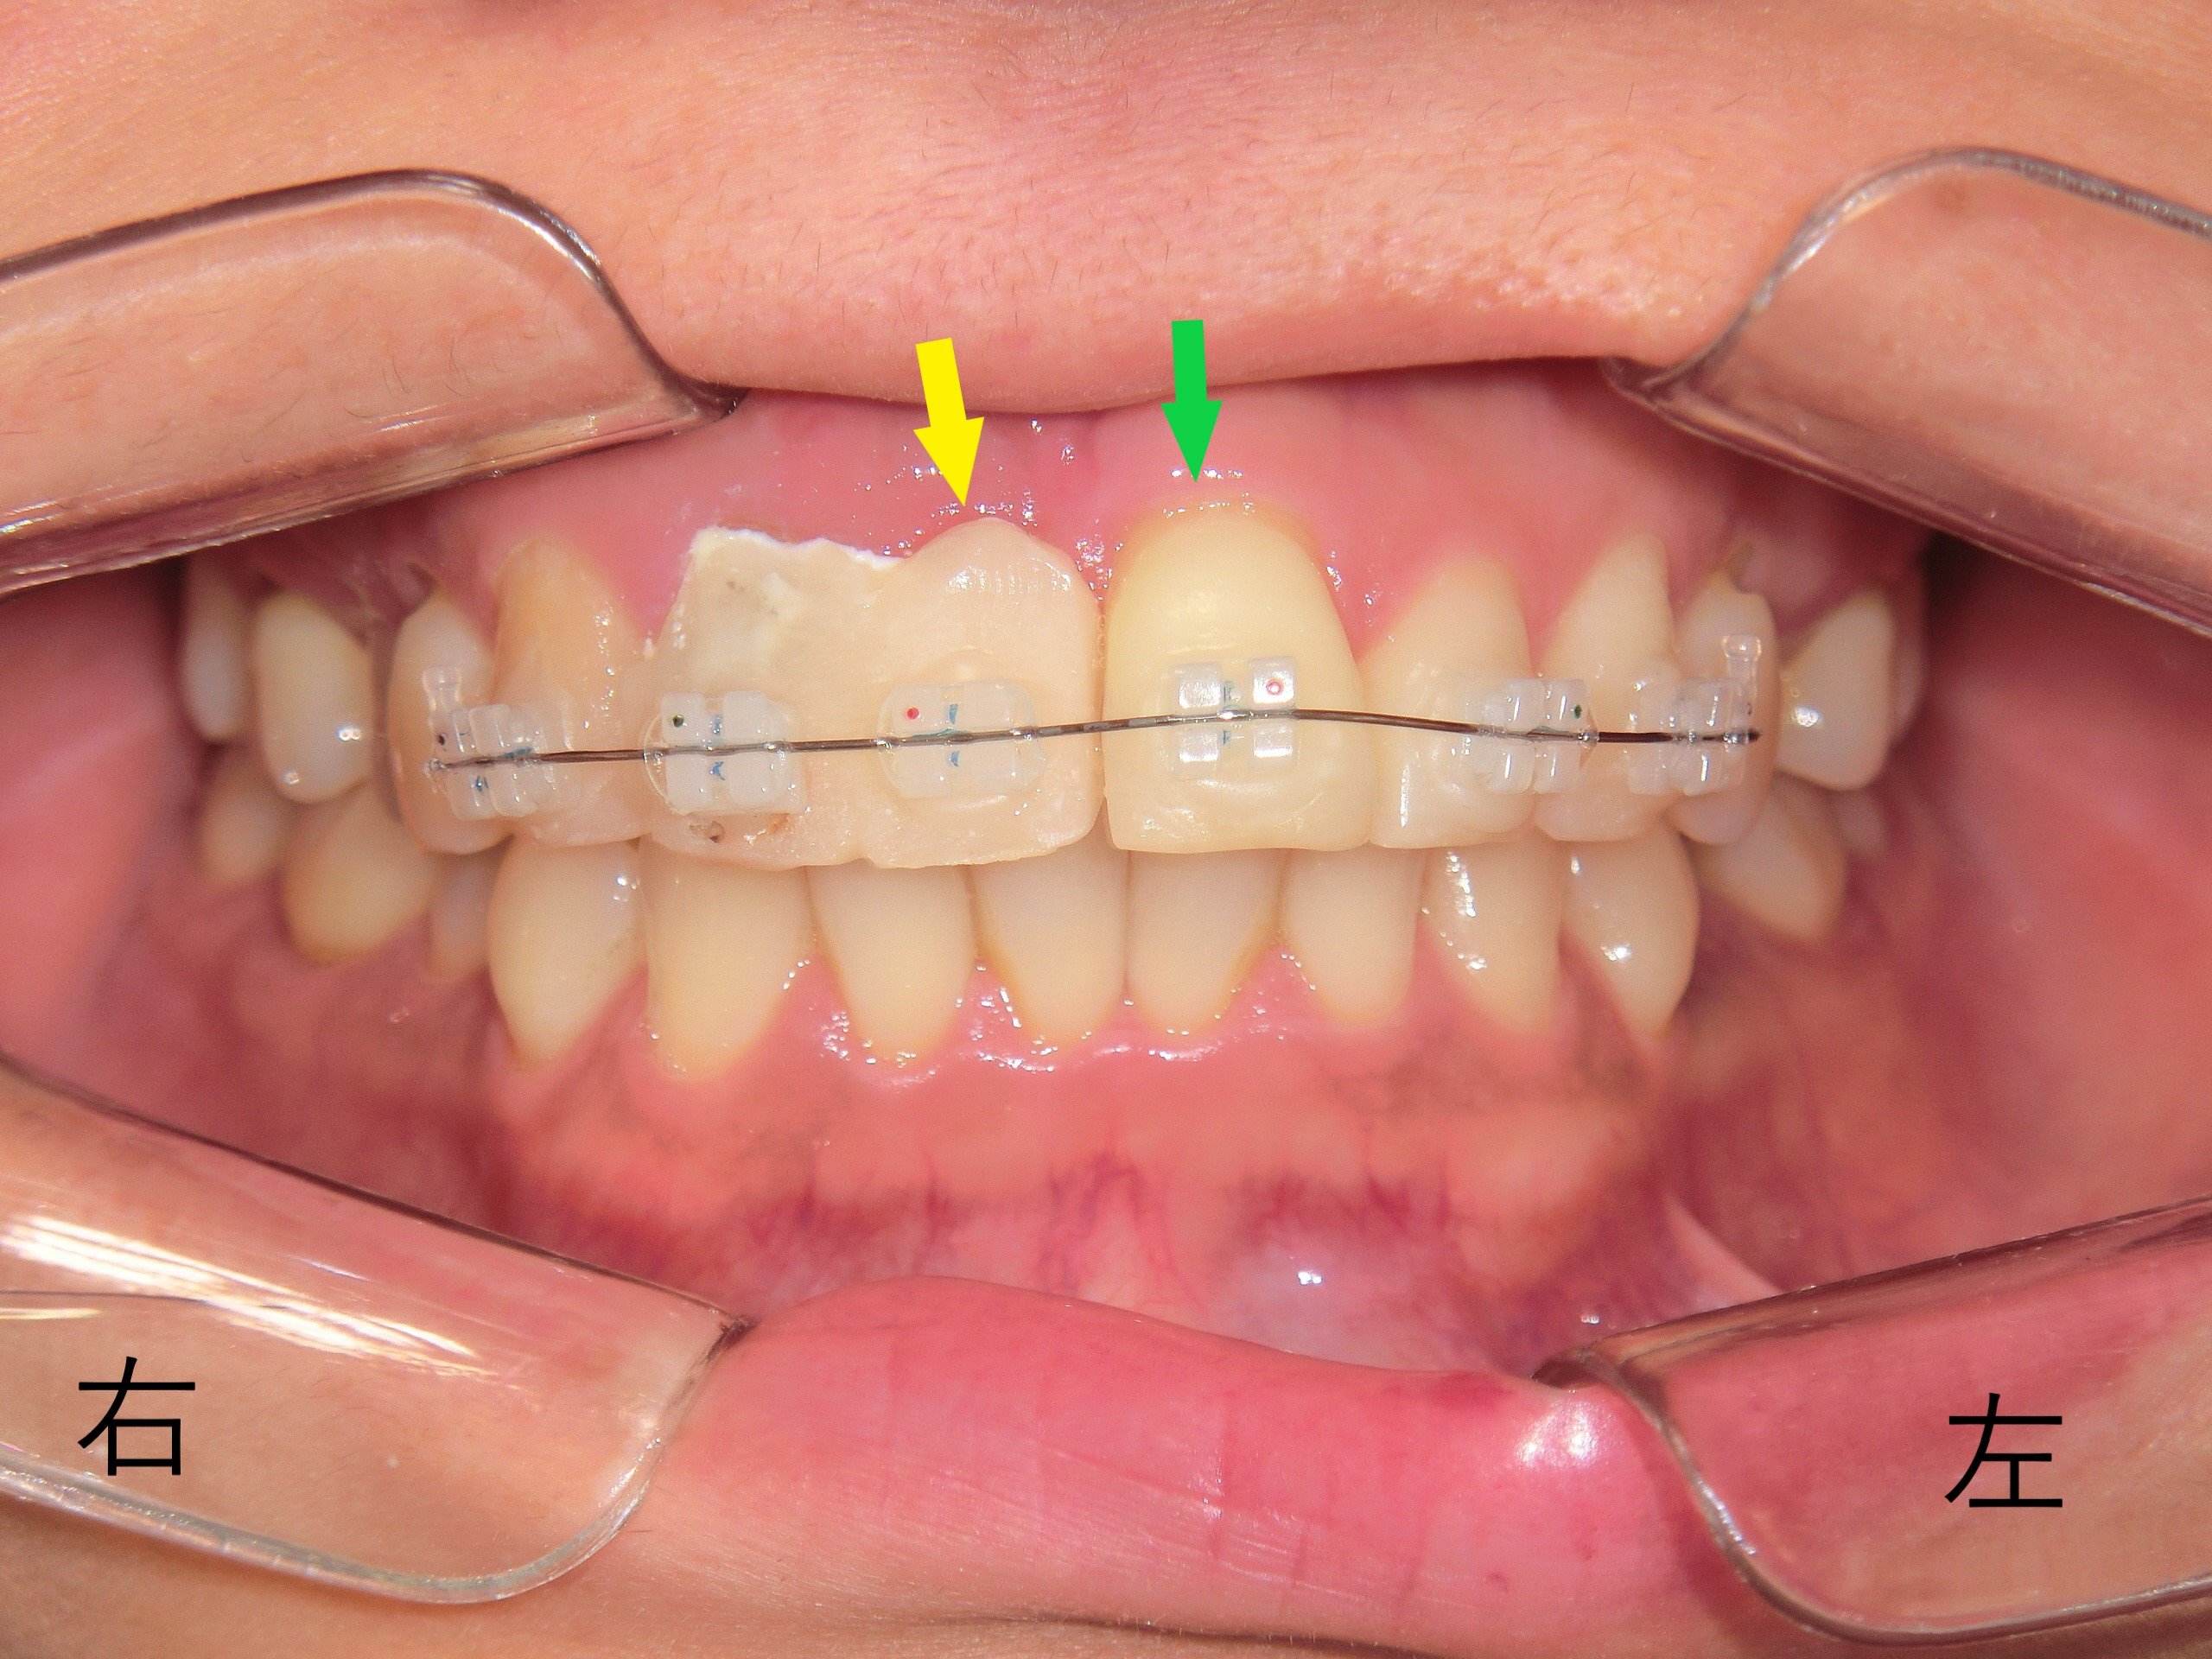

【治療過程の写真】

ブラケットとワイヤーを装着した直後の写真では、左上前歯の突出が正面からではわかりにくい場合もありますが、角度を変えることで明確に確認できます。